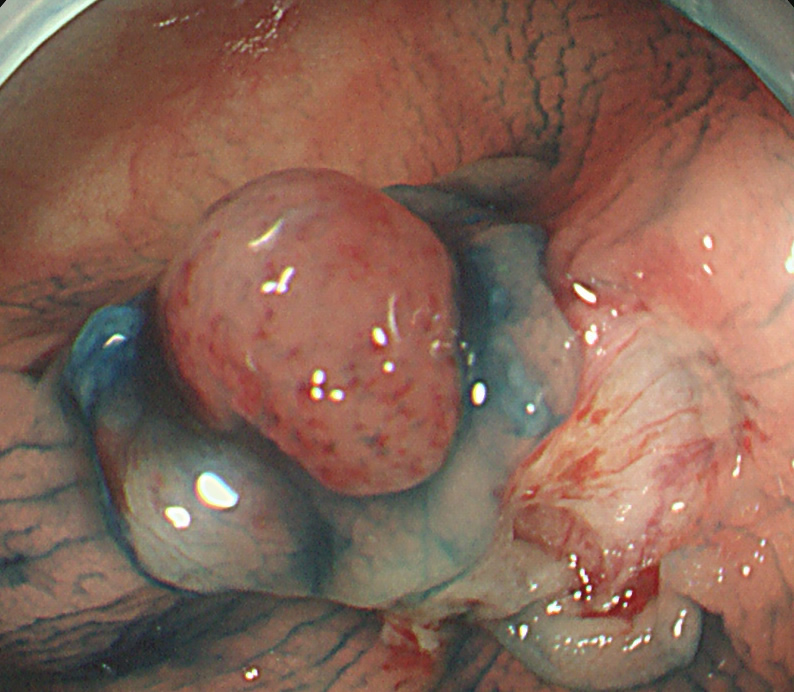

実際の写真です。

「生切り」なので、当然、内視鏡中(切除時)は出血します(患者さんが不安になります)。しかし、出血は数分で止まり、晩期出血は、まずありません。